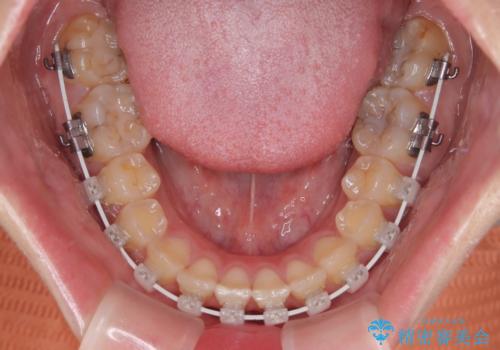

- 審美装置

ワイヤー矯正でもマウスピース矯正でも可能でしたが、短期間で、自身の手を煩わせることなく治療を行いたいとのことで、ワイヤー装置にて矯正治療を行うこととしました。

僅か8ヶ月という短期間で、綺麗な歯列に仕上がりました。